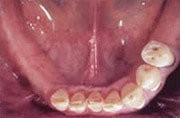

Unterkiefer mit Teilbezahnung

Früher wäre hier nur eine herausnehmbare Teilprothese infrage gekommen.

herausnehmbare Teilprothese mit Klammern

Eingesetzte Teilprothese

Sichtbare Klammern an den Frontzähnen